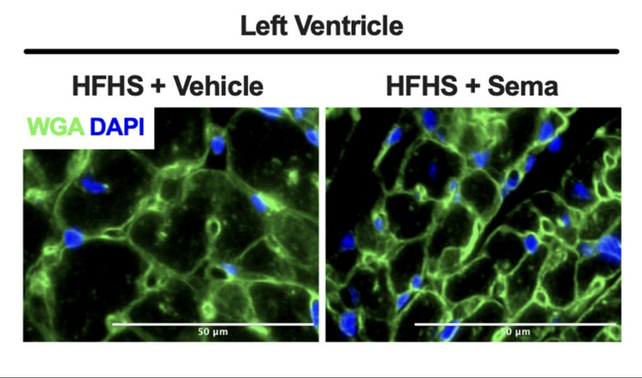

In 2024, a study in mice revealed that semaglutide can have a shrinking effect on a type of muscle specific to mammalian hearts. Other studies have also found significant skeletal muscle loss, along with the desired fat loss and anti-diabetic effects of this molecule.

The cardiomyocyte area of mice without (left) and with semaglutide treatment (right). (Martens et al., The Lancet, 2024)

The cardiomyocyte area of mice without (left) and with semaglutide treatment (right). (Martens et al., The Lancet, 2024)